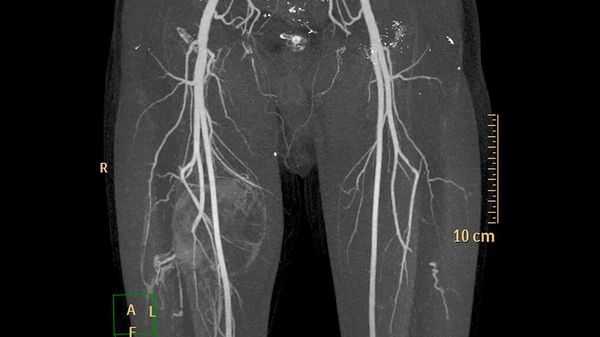

Дополнительные методы обследования для выявления поверхностных и локализованных поражений, как правило, не требуются. В случае же обширного распространения при первоначальной диагностике, для оценки костной ткани и при планировании лечения применяют методы визуализации:

- ультразвуковое исследование (УЗИ) и магнитно-резонансную томографию (МРТ) для первоначальной диагностики [12] ;

- рентгенографию для обнаружения типичных для венозных мальформаций флеболитов;

- компьютерную томографию (КТ) для оценки костной ткани;

- рентгеноконтрастную флебографию (введение в просвет вен рентгеноконтрастного вещества) для планирования лечения [7] .